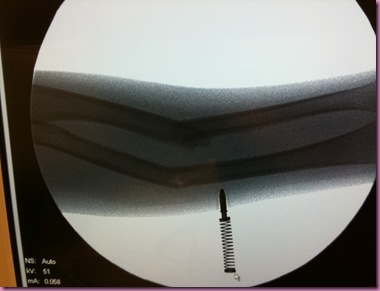

The X-ray picture reminds me of when I got my broken arm

They took another x-ray to make sure my arm was OK.